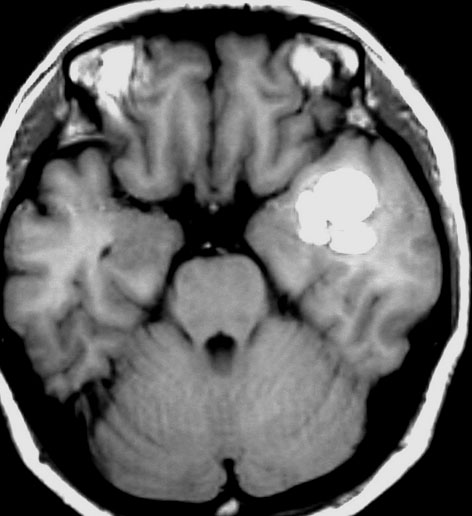

多発性海綿状血管腫 multiple cavernous hemangioma

家族性海綿状血管腫 familial cavernous hemangioma

この様な無数の海綿状血管腫を見ることがあります。多くの場合は家族性(遺伝性)の海綿状血管腫です。200個を超える海綿状血管腫があっても普通に何の障害もなく暮らしている患者さんもいます。脊髄の中にも発生しますから,脊髄のMRIもしていただきましょう。

小さな多発性の海綿状血管腫は,T2*(ティーツースター)という左の画像では見えるのですが,右にあるような普通のT1強調画像というのでははっきりみえません。

家族性多発性海綿状血管腫の患者さんは,小さな出血など生じても安易に手術を受けないようにしましょう。どの血管腫が大きくなるのかは全く予想できませんし,とても多数回の手術を受ける結果になるかもしれないからです。